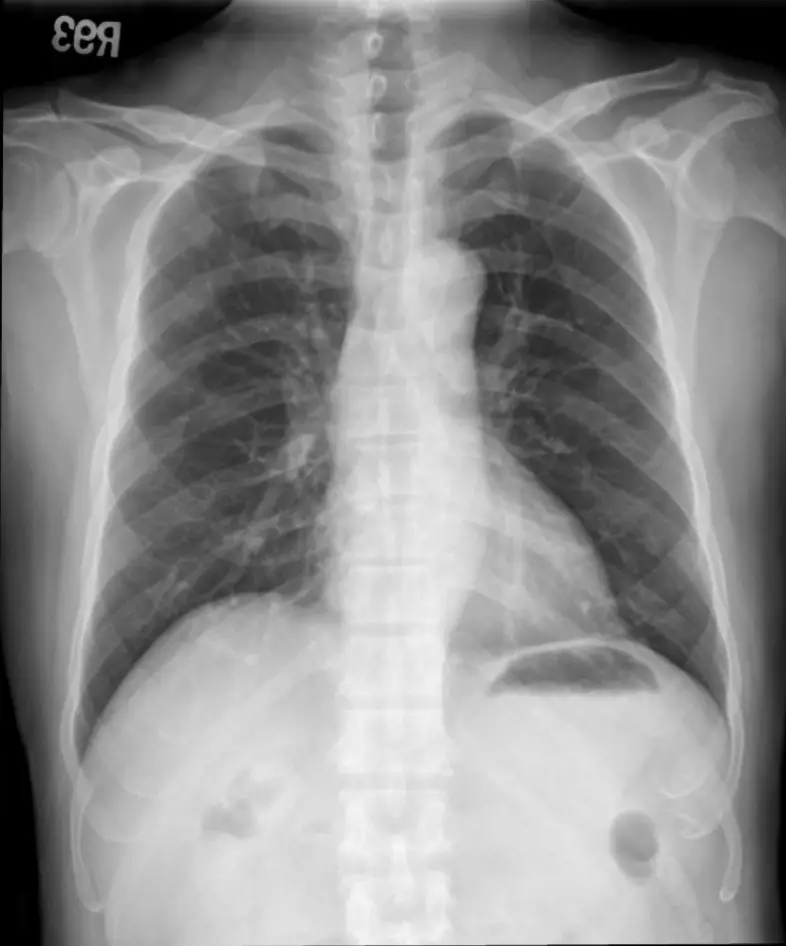

胸部X光片:心臟大小正常,肺野清晰,無肺水腫或肺炎徵象,未見主動脈剝離或鈣化明顯異常,顯示無急性肺部併發症。